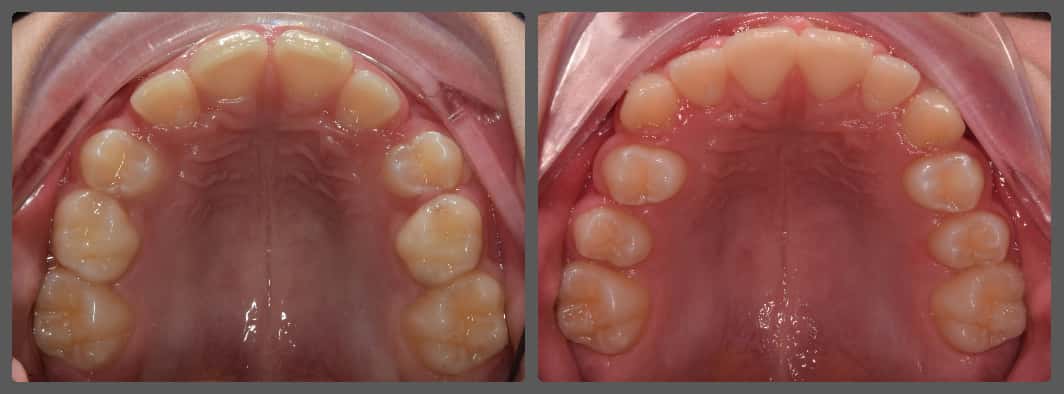

Zoli torlódott alsó fogai miatt szeretett volna fogszabályozó készüléket. Régebben 2 db felső kisőrlő fog eltávolításával már fogszabályozták, azonban az alsó fogív eltérései jelentősek voltak. A torlódás mellé közepes mértékű mélyharapás társult, valamint a bal oldali kisőrlő fogaknál non-occlusiot figyeltem meg. Ez azt jelenti, hogy esetünkben a felső első kisőrlő fog az alsó első és második kisőrlő fog közé, de azok külső felszínére harap. Ez a felső fogat kifelé, az alsókat befelé, a nyelv felé dönti és hosszútávon súlyos elváltozást okoz. Alsó-felső Pitts21 rögzített fogszabályzóval, intermaxilláris gumihúzással, harapásemelőkkel és tolórugókkal Zoli fogait nagyon gyorsan, 13 hónap alatt sikerült tökéletes pozícióba szabályoznunk, mind esztétikai, mind funkcionális szempontból (persze ehhez kellett a töretlen lelkesedése, együttműködése is). A kezelés végén az alsó fogívre fix retainert helyeztem fel az elért állapot megőrzésére. A végeredmény úgy gondolom mindent elmond!